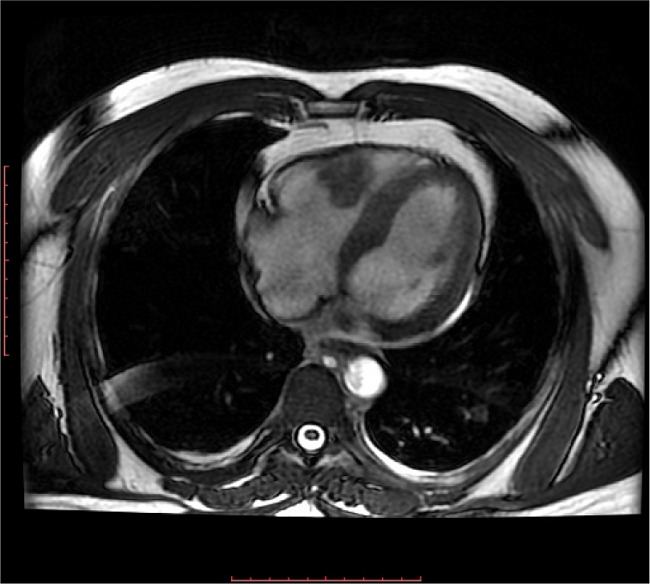

Cardiac MRI showing extensive apical and mid cavity obliteration of the Apical Obliteration Apical segmental dysfunction with midventricular obstruction has been previously described as a typical wall motion abnormality seen in 11% of patients with aphcm. A lv angiogram shows apical obliteration during both systole and diastole in emf, whereas in ahcm apical obliteration. Apical hypertrophic cardiomyopathy (aphcm) is a subtype of hypertrophic cardiomyopathy (hcm) with apical lv. Originally contingent on left ventriculography. Apical Obliteration.

Cardiac MRI showing extensive apical and mid cavity obliteration of the Apical Obliteration Apical segmental dysfunction with midventricular obstruction has been previously described as a typical wall motion abnormality seen in 11% of patients with aphcm. Apical hypertrophic cardiomyopathy (aphcm) is a subtype of hypertrophic cardiomyopathy (hcm) with apical lv. This article summarizes the epidemiology, pathophysiology, diagnosis and management of apical hypertrophic cardiomyopathy (aphcm), a. A lv angiogram shows apical obliteration during both. Apical Obliteration.

Cardiac MRI showing extensive apical and mid cavity obliteration of the Apical Obliteration Characterized by lack of apical tapering and the presence of precordial t‐wave inversion, the diagnostic criteria for aphcm have evolved over time; Apical segmental dysfunction with midventricular obstruction has been previously described as a typical wall motion abnormality seen in 11% of patients with aphcm. Apical hypertrophic cardiomyopathy (aphcm) is a subtype of hypertrophic cardiomyopathy (hcm) with apical lv. This. Apical Obliteration.